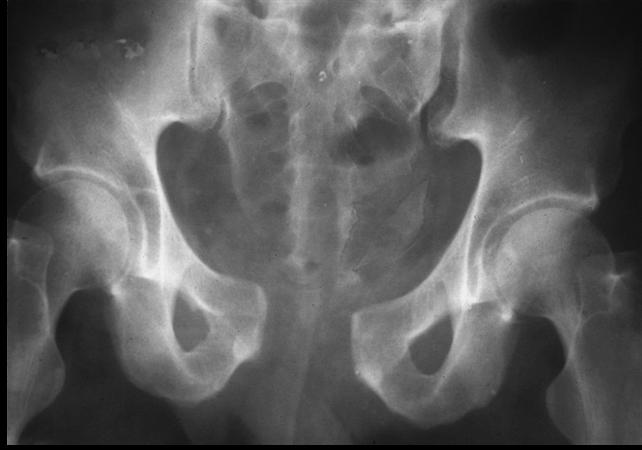

LC (Lateral compression)는 anterior injury가 rami 에서 시작되는 형태입니다.

LC I : sacral fracture 가 같은 쪽에 생깁니다.

LC II : crescrent fracure 가 같은쪽에 생깁니다.

LC III : I+II+ 반대쪽 open book injury 가 동반됩니다.